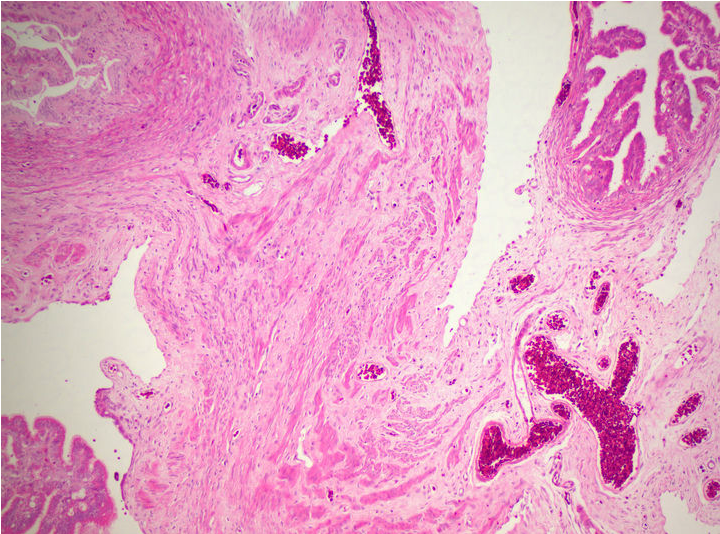

生物顯微鏡下的卵巢病理切片

病理切片是病理科醫(yī)生確診病癥的重要工具,觀察病理切片一般使用生物顯微鏡明場觀察,一款好的病理切片顯微鏡,不僅要求使用舒適,還要成像清晰。在生物顯微鏡ML31的觀察下,經(jīng)過HE染色的卵巢切片呈粉紅色,并呈現(xiàn)出豐富而復(fù)雜的細節(jié)。

卵巢,作為女性生殖系統(tǒng)的重要器官,負責產(chǎn)生卵子和分泌性激素。透過生物顯微鏡ML31,我們可以看到許多不同種類的細胞。其中較突出的是卵原細胞,這是卵巢中產(chǎn)生卵子的母細胞。在染色切片中,卵原細胞呈現(xiàn)出較大的體積和較深的染色,與其他細胞有所區(qū)別。

通過生物顯微鏡ML31觀察卵巢染色切片,我們可以了解卵巢的基本結(jié)構(gòu)和功能。這不僅有助于我們對生殖系統(tǒng)的理解,也為研究卵巢疾病的病因、病理和治療方法提供了重要依據(jù)。